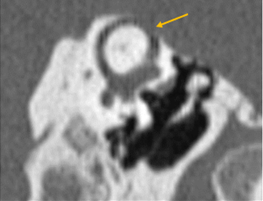

Figura 5. Ventana oval obliterativa de oído derecho en un corte coronal de oído medio |

Figura 6. Oídos derechos con obliteración de ventana redonda (flecha amarilla) |